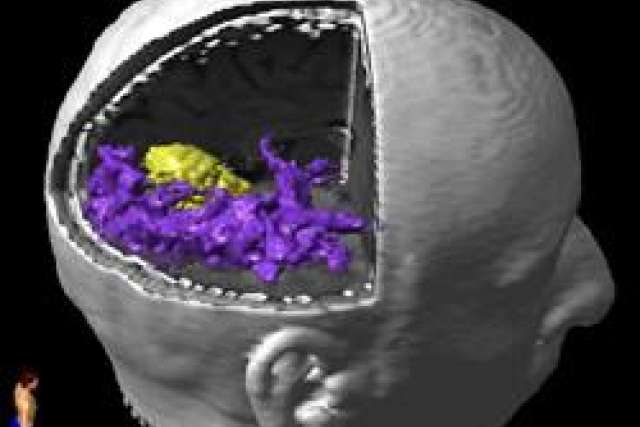

Dr. Linda Liau met Robert and decided that surgical resection of the mass would be the most appropriate treatment choice given his symptoms and increasing size of the lesion. As the mass was located in an area that would result in obvious neurologic deficits if disrupted (visual cortex), preoperative functional MRI (fMRI) and diffusion tensor imaging (DTI) data was obtained in order to help map out the relation of the mass to critical visual fibers for navigation in the OR. This helps the surgeon intraoperatively by guiding resection and avoiding areas critical for neurologic function. [Purple = visual fibers; yellow = tumor].

Diffusion tensor imaging 3D view:

Diffusion tensor imaging 3D view of Robert's brain